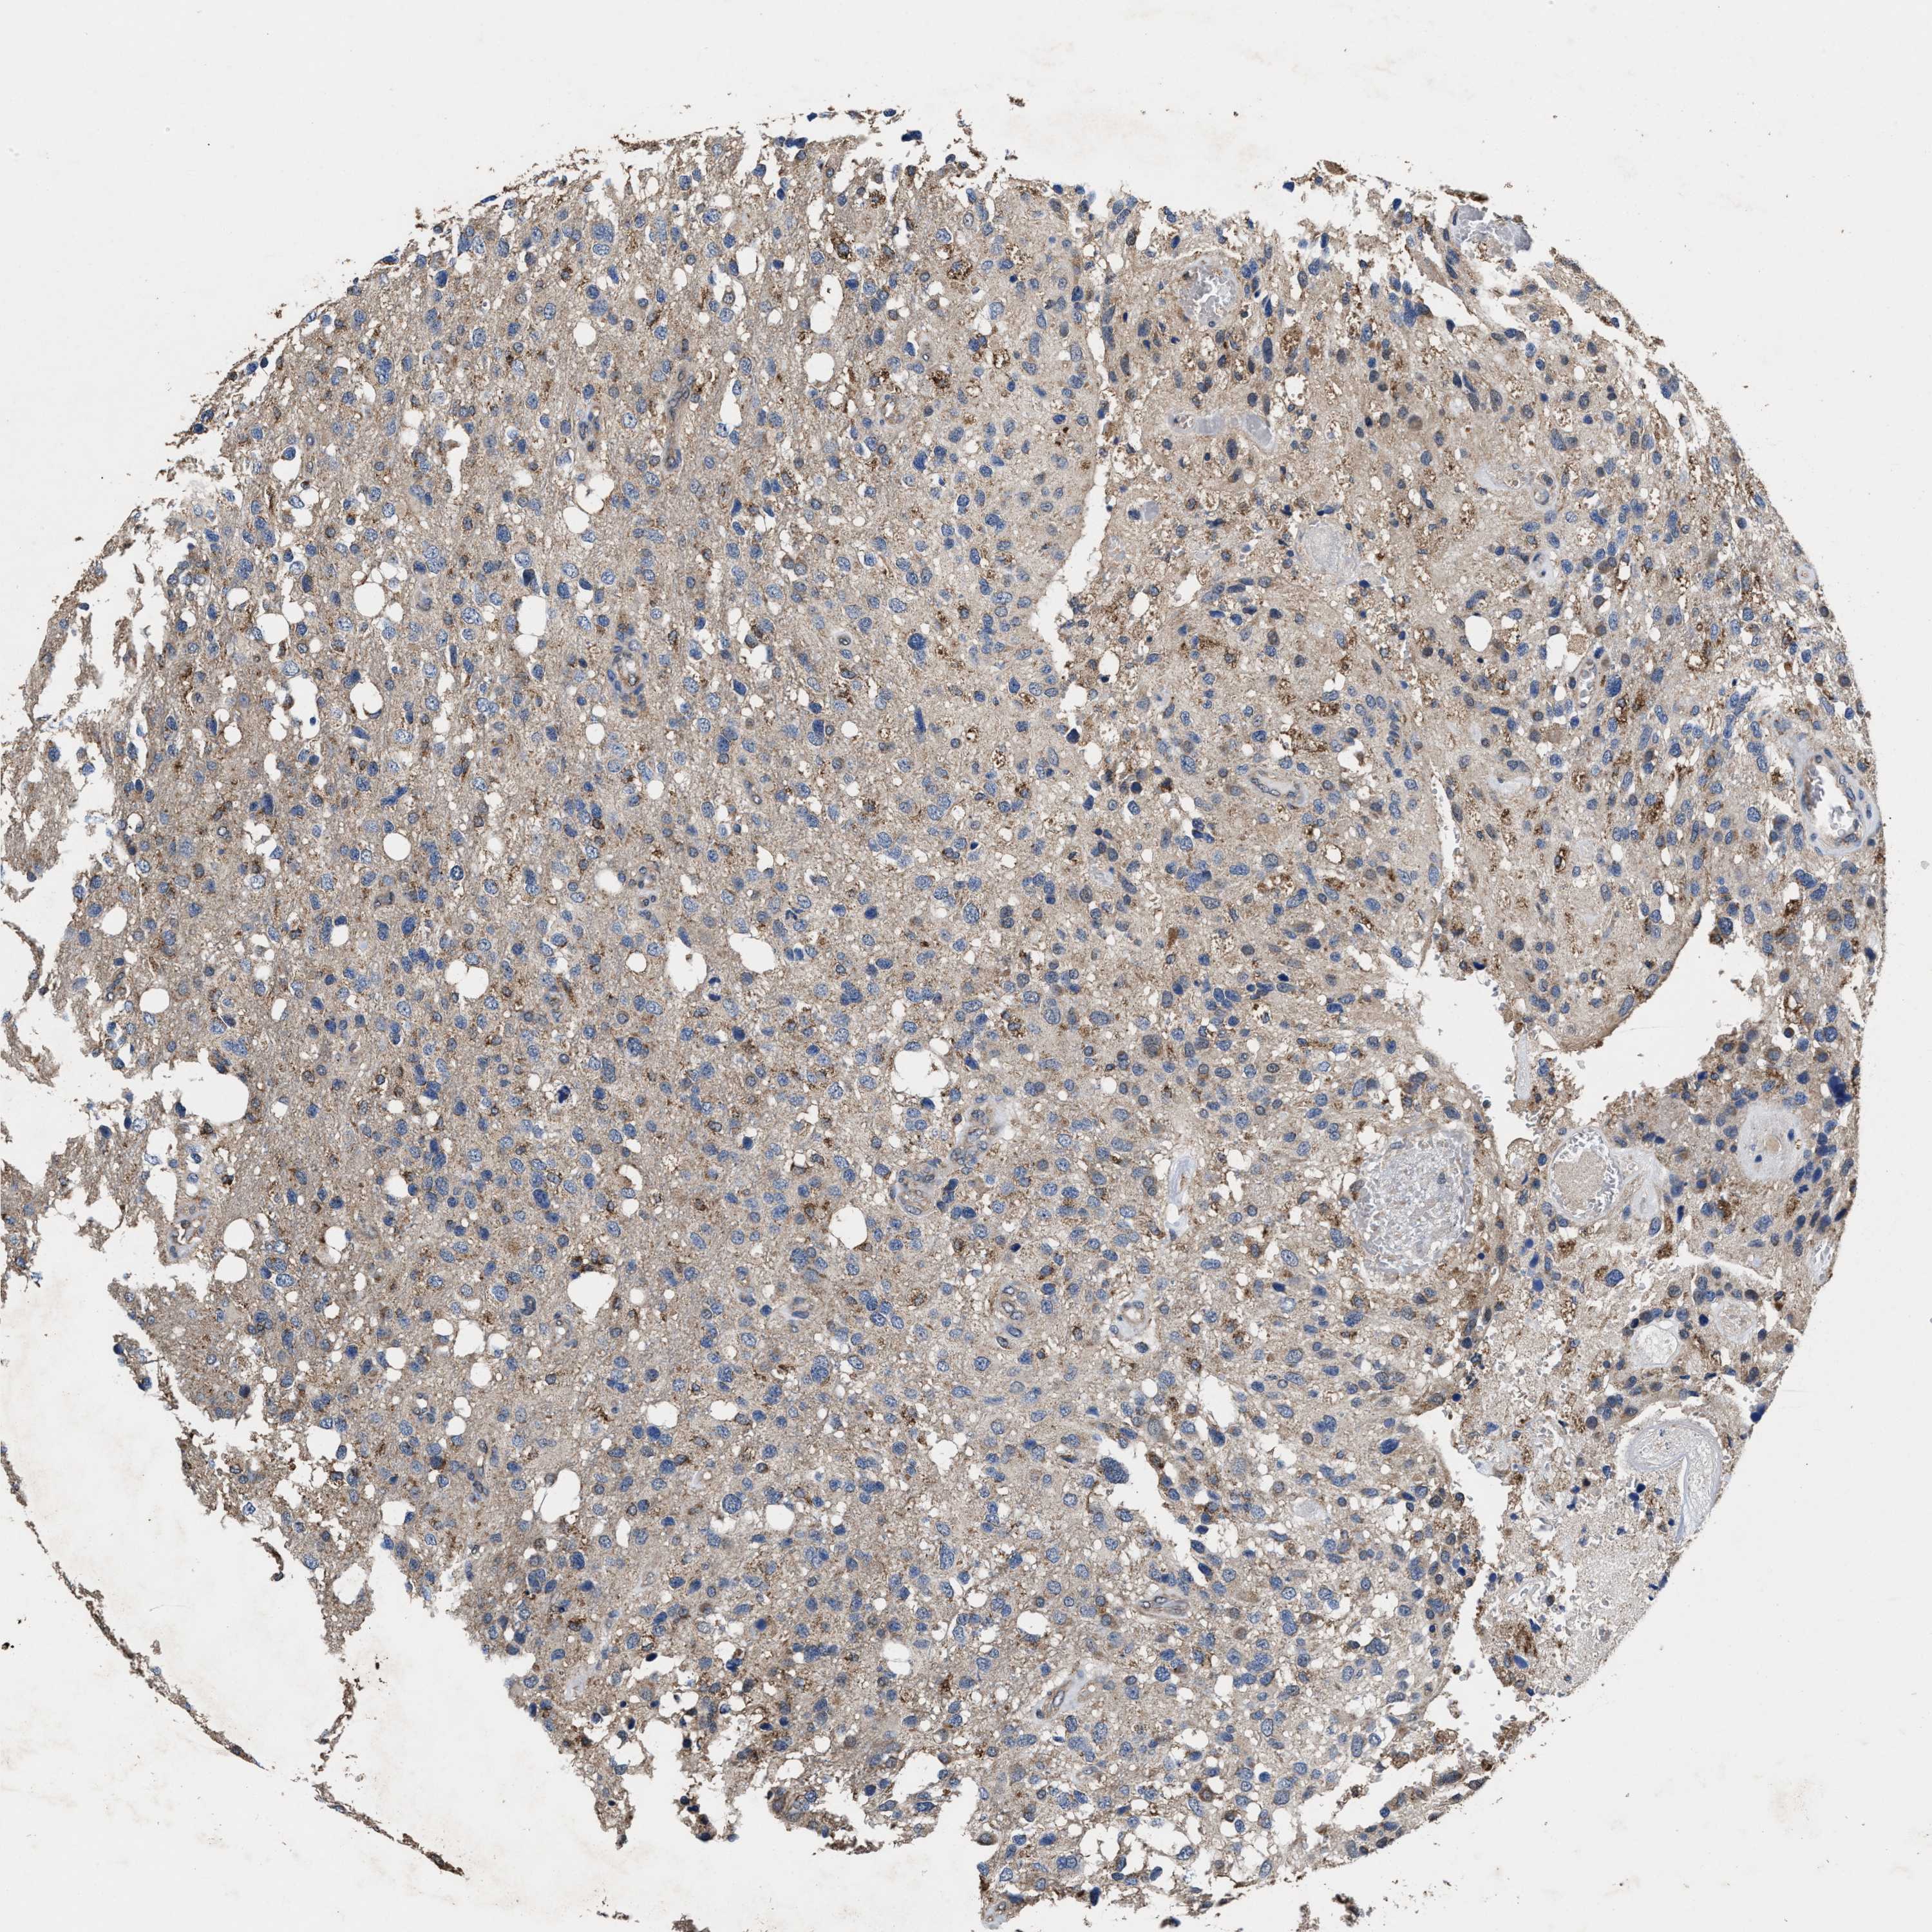

GLIOMA - Protein expressioni

A mouse-over function shows sample information and annotation data. Click on an image to view it in a full screen mode. Samples can be filtered based on level of antibody staining by selecting one or several of the following categories: high, medium, low and not detected. The assay and annotation is described here.

Note that samples used for immunohistochemistry by the Human Protein Atlas do not correspond to samples in the TCGA dataset.

Antibody stainingi

Antibody staining in the annotated cell types in the current human tissue is reported as not detected, low, medium, or high, based on conventional immunohistochemistry profiling in selected tissues. This score is based on the combination of the staining intensity and fraction of stained cells.

Each image is clickable and will lead to virtual microscopy that enables deeper exploration of all samples and also displays staining intensity scores, fraction scores and subcellular localization as well as patient and tissue information for each sample.

HPA022434

HPA022953

HPA022959

HPA028758

CAB007783

Glioma, malignant, High grade

Glioma, malignant, Low grade

Glioblastoma, NOS